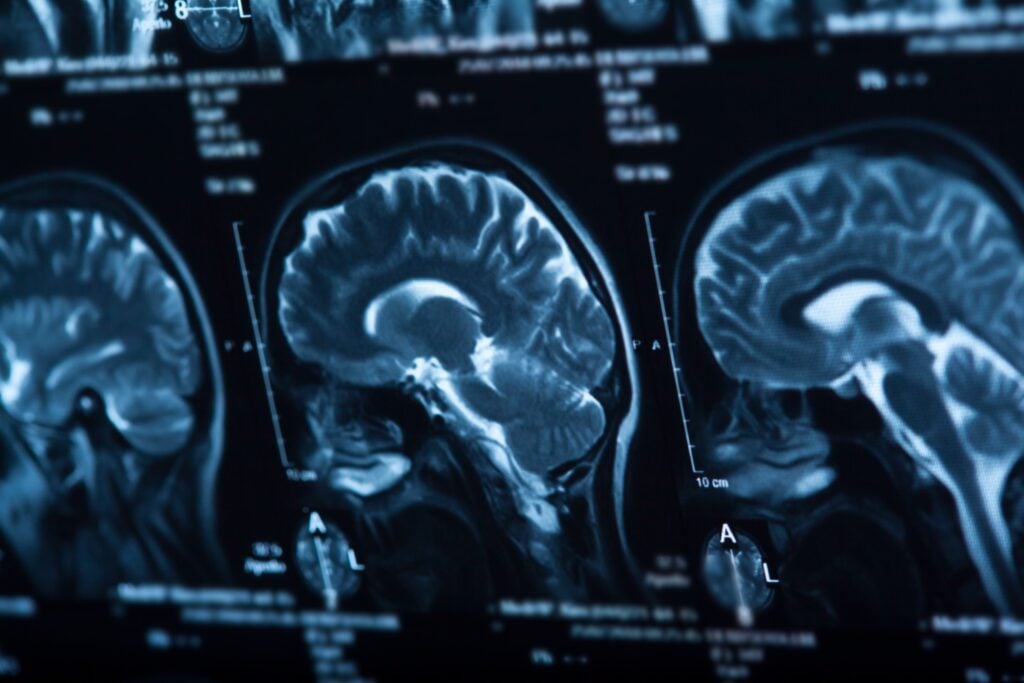

What Are Coup and Contrecoup Brain Injuries?

The terms coup and contrecoup are French words that mean “blow” and “counterblow.” In the context of brain injuries, these terms refer to injuries caused by an impact to the skull. Both coup and contrecoup brain injuries are closed brain injuries. This means that the skull is not fractured, broken, or punctured.

A coup injury occurs at the point of impact with an object. The force of the impact causes the brain to move within the skull and collide with the inside of the skull, bruising the brain tissue at that site. A contrecoup injury occurs on the opposite side of the brain from the point of impact. This happens because the force of the initial impact causes the brain to move within the skull, hitting the opposite side of the skull and causing injury to the brain tissue at that site.